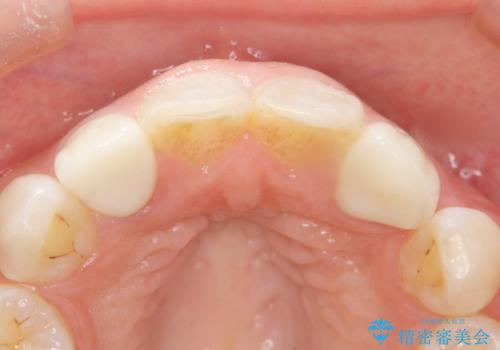

矯正せずに早く治したいという強いご希望により、セラミッククラウンによる補綴治療(上顎両側2の2本)を行いました。

天然歯のような自然な仕上がりに大変喜んで頂けました。

クラウンの種類:オールセラミッククラウン スペシャル